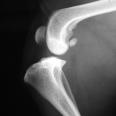

Die Orthopädie beschäftigt sich mit der Entstehung, Verhütung und Behandlung von angeborenen oder erworbenen Problemen des Bewegungsapparates. Die meist daraus resultierenden Lahmheiten werden bei uns umfassend abgeklärt. Hierbei kommen neben einer ausführlichen klinischen Lahmheitsuntersuchung auch weiterführende diagnostische Verfahren, wie Röntgen Computertomografie und Ultraschall zum Einsatz.